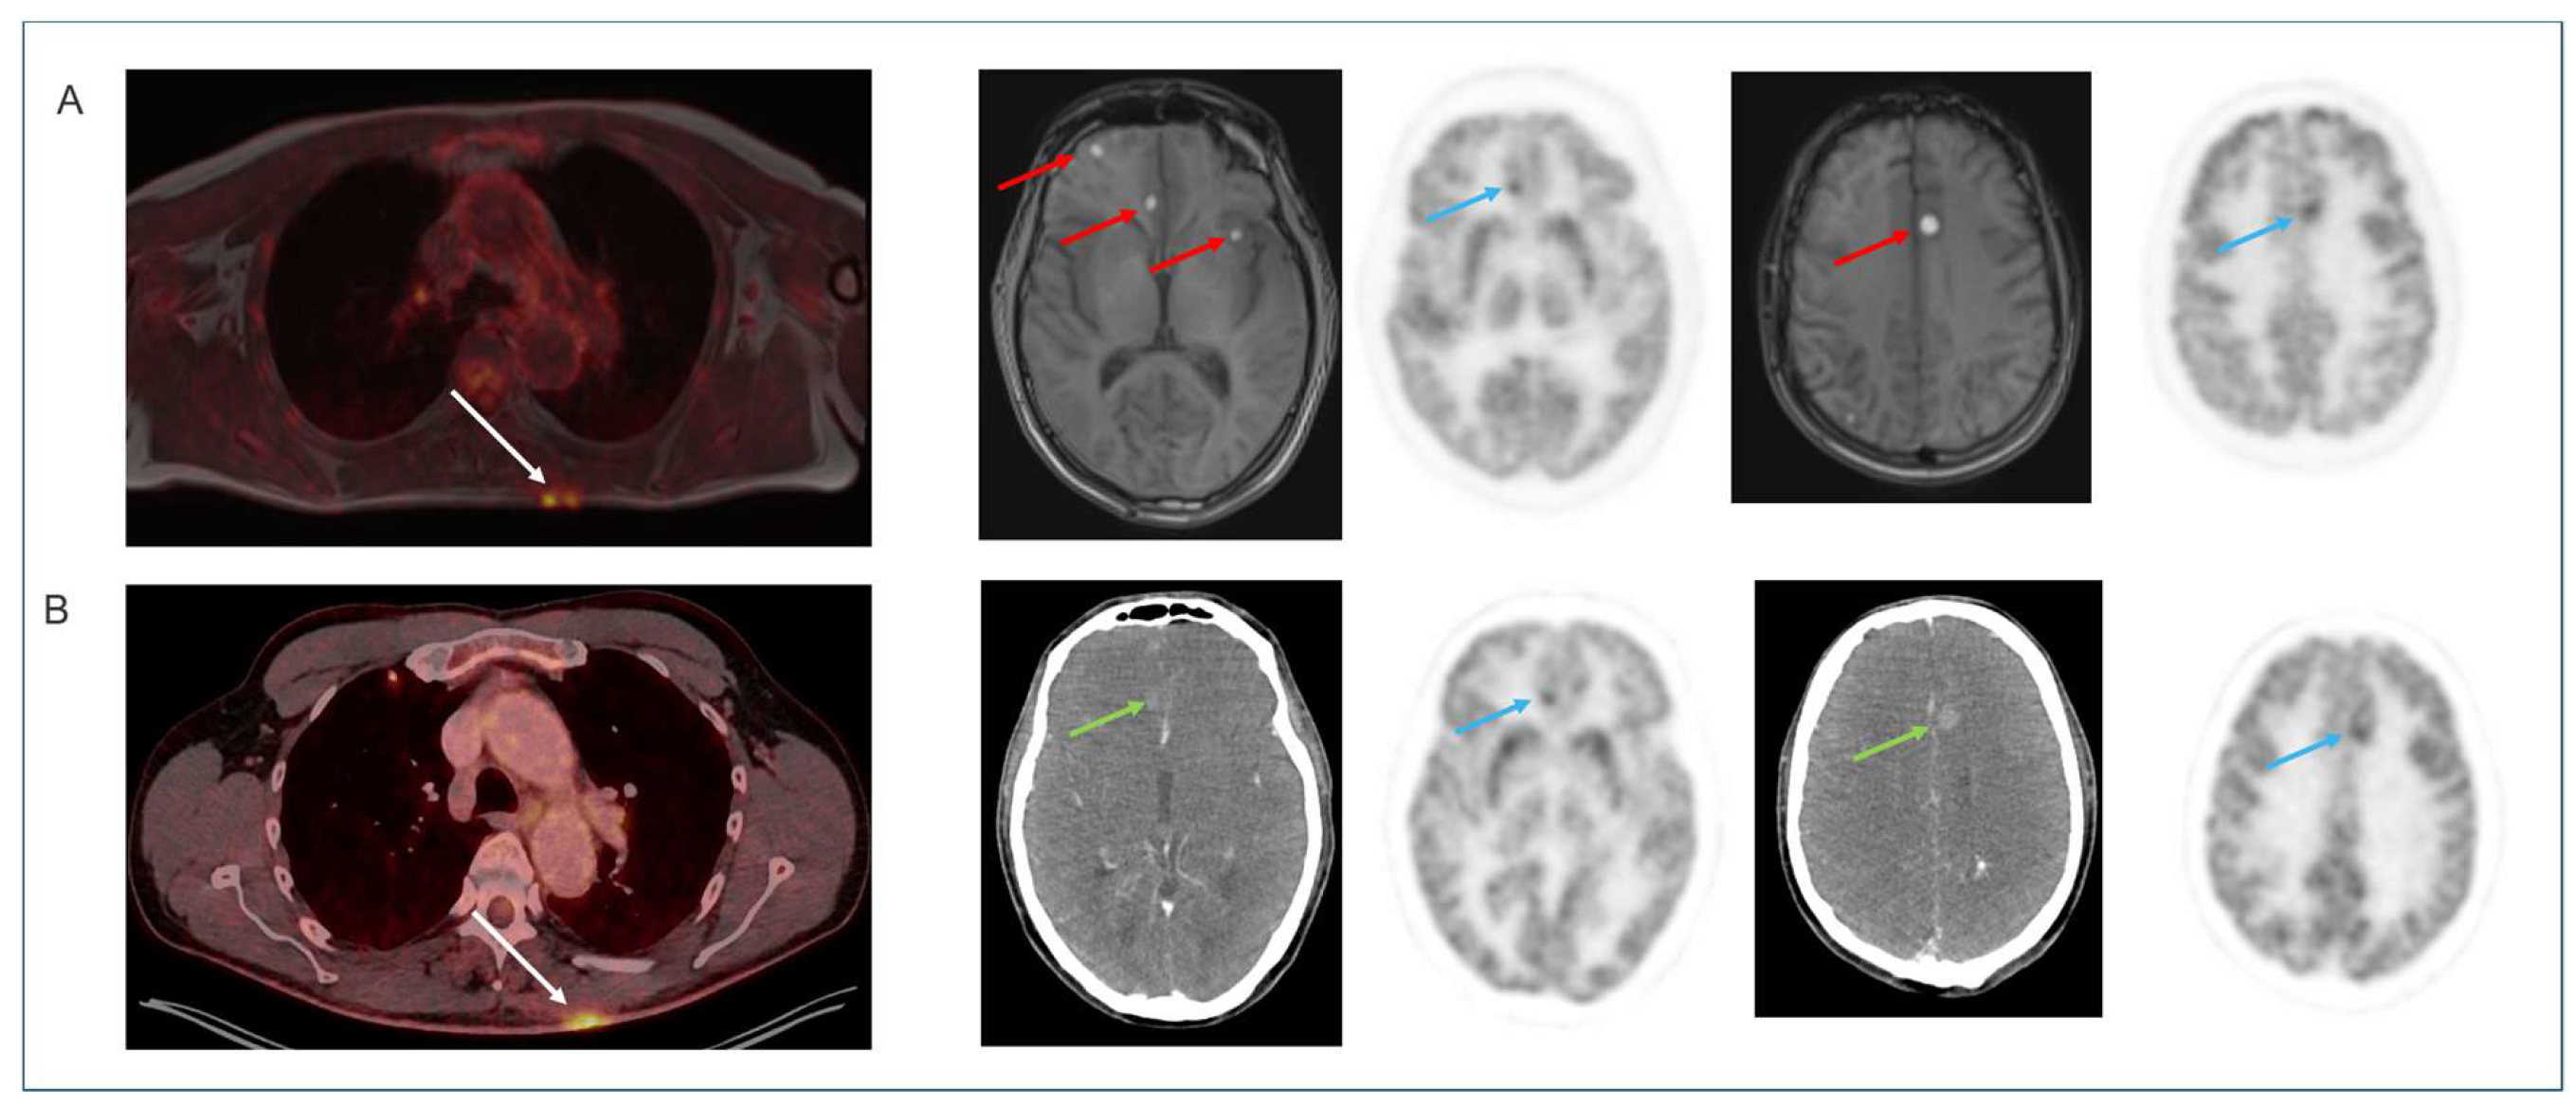

4.4. Non-Brain [18F]FDG Oncology Applications